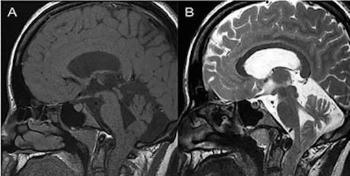

“No solamente el servicio de salud colapsa. Todo el sistema productivo (de México) podría colapsar en un momento dado con las secuelas. Simplemente, una de las secuelas que dura mucho tiempo y que es bastante inhabilitante, aunque no incapacitante, es el dolor de cabeza. El 58 por ciento de las personas que se han infectado reportan dolores de cabeza o neuralgias que les hacen perder concentración. De ahí en fuera hay toda una serie de síntomas que finalmente van a afectar la capacidad de producir y de laborar de las personas”, señaló el médico especializado en biología celular.

Pérdida de cabello, erupciones cutáneas, cansancio, dolores de cabeza, depresión, ansiedad, cambios de humor, desregulación del sueño, disfunción olfativa y gustativa, cognición alterada, deterioro de la memoria, anomalías de la función pulmonar como la fibrosis, inflamación del miocardio, disfunción ventricular y lesiones renales agudas son ejemplos de secuelas cada vez más ligadas al coronavirus.

De acuerdo con el análisis de reportes oficiales a nivel mundial, además de esos síntomas, el síndrome inflamatorio multisistémico en niños, los problemas cardiovasculares, pulmonares, renales, hepáticos, metabólicos relacionados con glucosa y neurológicos están entre las posibles secuelas de la Covid-19.